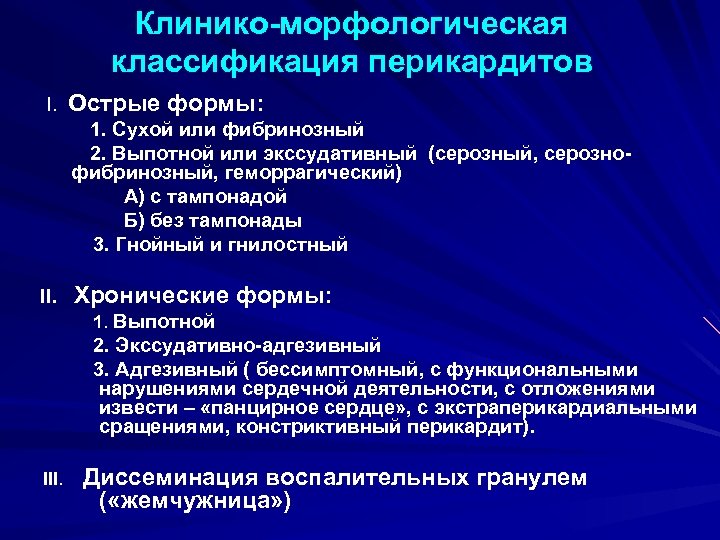

Клинико-морфологическая классификация перикардитов I. Острые формы: 1. Сухой или фибринозный 2. Выпотной или экссудативный (серозный, серознофибринозный, геморрагический) А) с тампонадой Б) без тампонады 3. Гнойный и гнилостный II. Хронические формы: 1. Выпотной 2. Экссудативно-адгезивный 3. Адгезивный ( бессимптомный, с функциональными нарушениями сердечной деятельности, с отложениями извести – «панцирное сердце» , с экстраперикардиальными сращениями, констриктивный перикардит). III. Диссеминация воспалительных гранулем ( «жемчужница» )